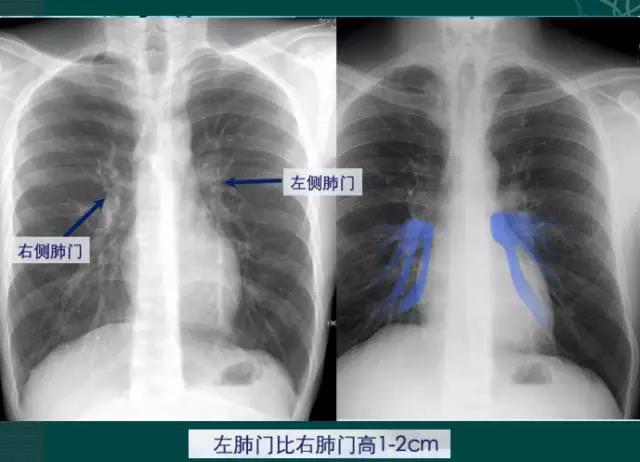

4.肺门的大小和位置

x线肺门指肺动脉、肺叶动脉、肺段动脉、伴行支气管以及肺静脉构成。

右肺门可分为上、下两部。上部约占1/3,由上肺静脉、上肺动脉及下肺动脉后回归支构成。上肺静脉下后干构成右上肺门的外缘;右肺门下部 约占2/3,由右下肺动脉干构成,其正常宽度不超过15mm,沿中间段支气管外缘平行向外下走行。右肺门上、下部相交形成一钝的夹角,称肺门角,正常该角顶清晰。如下图

左肺门亦分为上、下两部。上部由左肺动脉及其分支、左上叶支气管和左上肺静脉及其分支构成;下部由左下肺动脉及其分支构成,常被心影所遮盖。